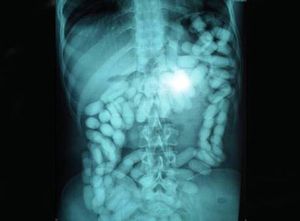

Now that’s some serious smuggling skills! An X-ray showing a man's intestines and stomach carrying a kilo of cocaine!! This man tried to smuggle one kilo of cocaine internally. One of the packages started leaking and he was rushed to hospital in a life-threatening condition and had to undergo three hours of intestinal surgery. Swipe left to see some of the capsules carried by the man.